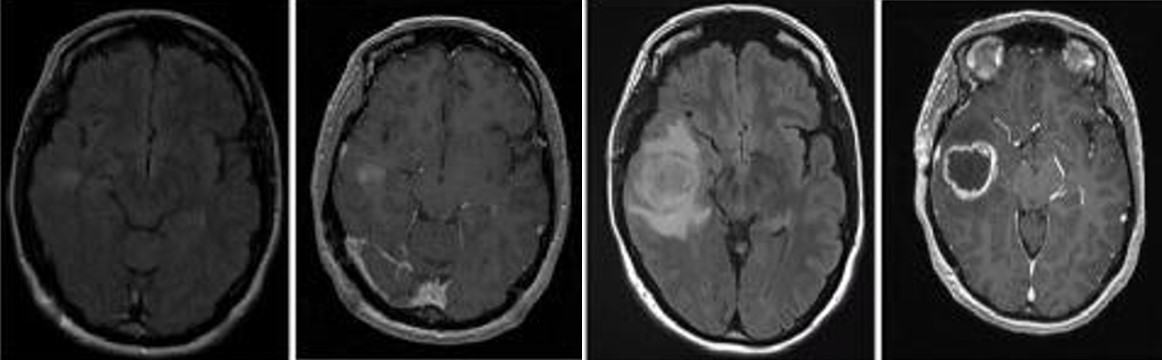

胶质母细胞瘤(Glioblastoma , GBM)是中枢神经系统中比较常见的神经上皮肿瘤,是恶性程度最高的原发性脑肿瘤也是最致命的实体瘤,被世界卫生组织归类为Ⅳ级胶质瘤。GBM 预后差,被诊断后的平均中位生存期为 14个月,其5年生存率为 5%。尽管目前在外科手术,放化疗等医学治疗手段取得了不错的进展,但在延长患者的生存期上仍未取得突破。因此,目前迫切需要筛选鉴定出有效的GBM生物标记物,探索GBM的治疗靶标并解析GBM的发病机理,为GBM的早期诊断及预后评估提供新策略以延缓患者的生存期。

崔红娟教授团队就GBM标志物的筛查、鉴定以及如何管控EGFR在GBM的表达开展了深入研究。首先, GBM患者组织的免疫组化病理检测以及生物信息学分析发现一种能够参与异染色质形成的H3组蛋白甲基化阅读器CBX3(Chromobox 3)在GBM患者中异常高表达,并且与GBM的预后和恶性分级密切相关。功能检测表明了CBX3 在体外和体内显著促进 GBM 细胞的增殖、侵袭和肿瘤发生。从机制上来说,我们通过Ch-IP和Co-IP等一系列生物技术实验证明了CBX3促进GBM 的恶性进展是EGFR 依赖性的,并且进一步揭示了GBM患者发病机理的一条全新的信号通路CBX3-PARK2/STUB1-EGFR。该研究不仅丰富了GBM表观遗传学的研究,也为该信号通路作为GBM潜在治疗靶点的可行性提供了坚实的依据。iQQtv